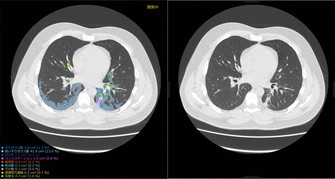

同社は2017年からCT画像をAIに分析させる技術研究を進めてきた。新型コロナ肺炎は、肺に「すりガラスのような影」が観察される特徴があり、その患者がコロナ肺炎なのか、それ以外の肺炎なのかを識別する技術に応用した。最終的に診断を下すのは医師だが、AI画像診断システムがCT画像の疑わしい部分に印をつけるなど、医師の負担軽減を期待できる。

同社が2月以降、コロナ肺炎を含む中国の患者のCT画像約8700人分をAIシステムに分析させたところ、患者1人につき最短…